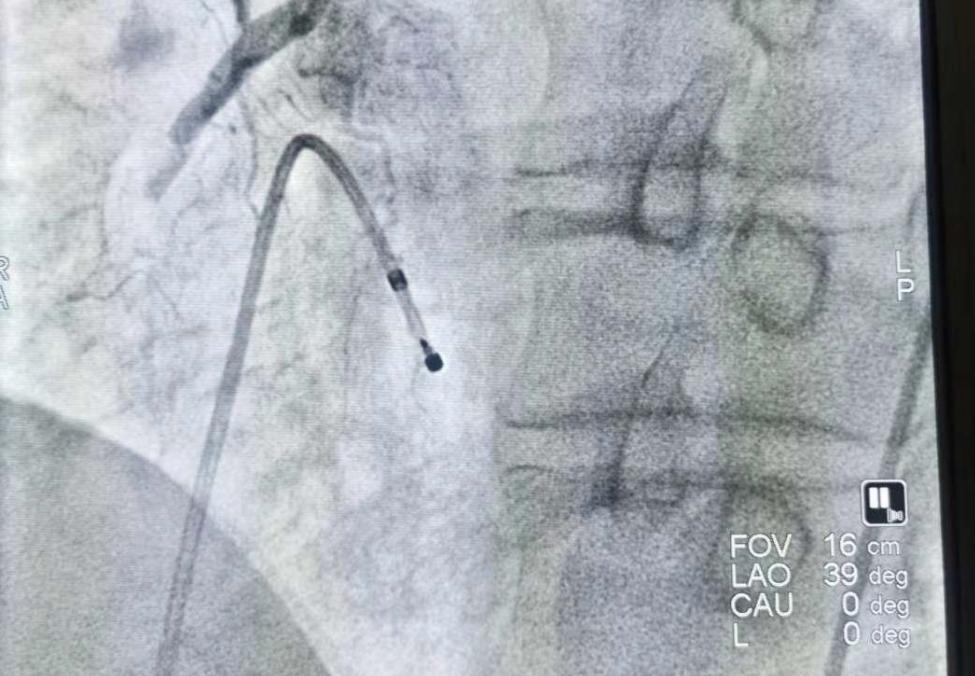

心内科医生立刻准备急诊介入手术,就在准备手术的时候,患者突发连续两次室颤。惊险万分,好在医生技术精湛,通过造影发现,患者心脏右侧冠脉近端完全闭塞。紧急植入支架后,患者安全返回病房。